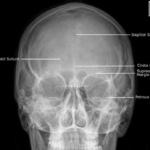

Las radiografías, generalmente llamadas rayos X, producen imágenes como sombras de huesos y ciertos órganos y tejidos. Las radiografías son muy buenas para detectar problemas óseos. Pueden mostrar algunos órganos y tejidos blandos; sin embargo, la MRI y la CT suelen crear mejores imágenes de los mismos. Aun así, las radiografías son rápidas, fáciles de obtener y menos costosas que los otros estudios, por lo que se pueden usar para obtener información rápidamente.

Un tubo especial dentro de la máquina de rayos X emite un haz de radiación controlada. Los tejidos del cuerpo absorben o bloquean la radiación en diferentes grados. Los tejidos densos como los huesos bloquean la mayor parte de la radiación, pero los tejidos blandos, como la grasa o los músculos, bloquean menos radiación. Después de pasar por el cuerpo, el haz alcanza una pieza de un fragmento de película o un detector especial. Los tejidos que bloquean altas cantidades de radiación, como los huesos, aparecen como áreas blancas en un fondo negro. Los tejidos blandos bloquean menos radiación y aparecen en tonos de gris. Los órganos que contienen principalmente aire (como los pulmones) aparecen en negro. Los tumores son por lo general más densos que el tejido que los rodea, por lo que suelen verse en tonos grises más claros.